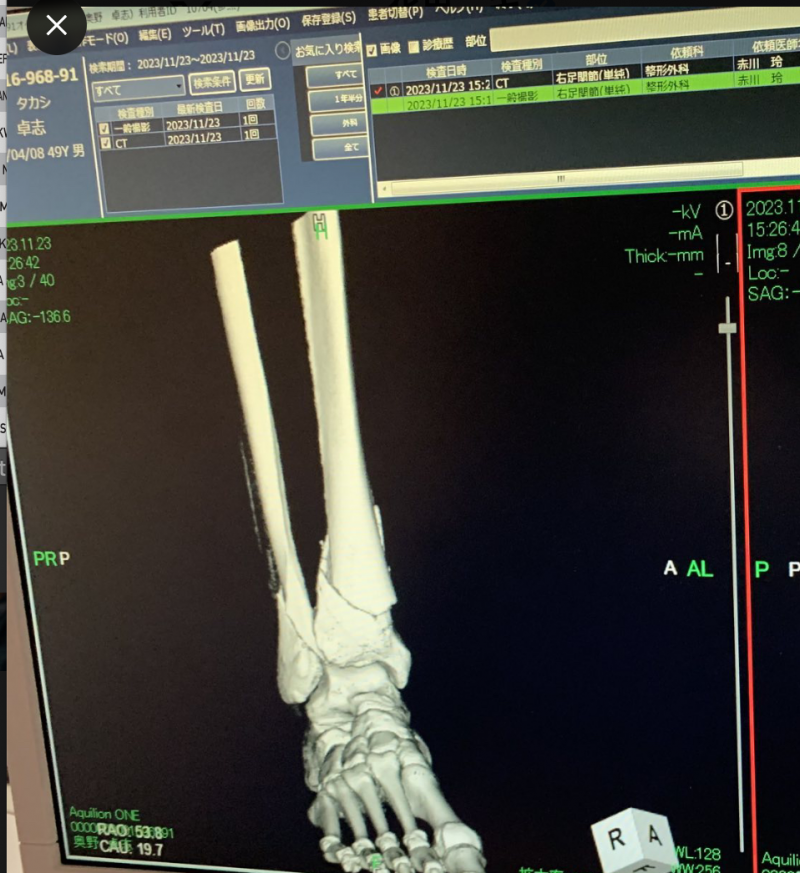

脛骨(けいこつ)と腓骨(ひこつ)両方折れた。右下に患者・奥野の名が(ごぼうの党 公式Xより)